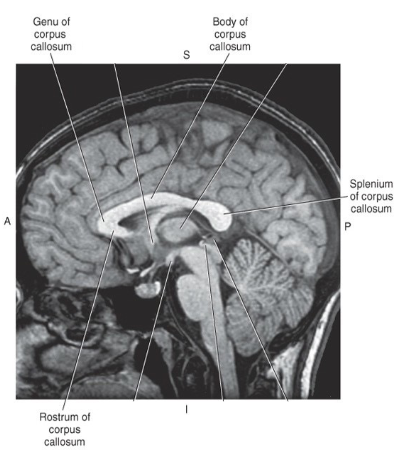

Corpus Callosum

• important white matter commissural tract

• components: rostrum, genu, body, splenium

<ul><li><p>important white matter commissural tract</p></li><li><p>components: rostrum, genu, body, splenium </p></li></ul><p></p>